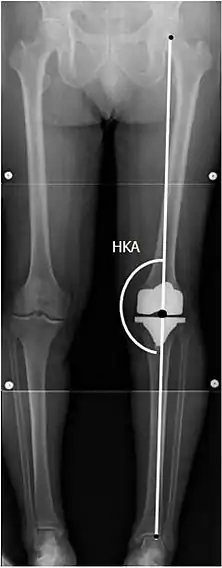

Para indicar el reemplazo de rodilla en caso de osteoartritis, su clasificación radiográfica y la gravedad de los síntomas deben ser sustanciales. Dicha radiografía debe consistir en radiografías en carga de ambas rodillas: AP, lateral y 30 grados de flexión. Es posible que las proyecciones AP y lateral no muestren un estrechamiento del espacio articular, pero la vista en flexión de 30 grados es más sensible al estrechamiento. También se utilizan proyecciones de longitud completa para ajustar la prótesis para proporcionar un ángulo neutro para la extremidad inferior distal. Dos ángulos utilizados para este propósito son:

- Ángulo cadera-rodilla-eje (CRE),[8] un ángulo formado entre una línea que pasa por el eje longitudinal de la diáfisis femoral y su eje mecánico, que es una línea desde el centro de la cabeza femoral hasta la muesca intercondilar de la diáfisis femoral. fémur.[10]

- Ángulo cadera-rodilla-tobillo (CRT),[9] que es un ángulo entre el eje mecánico femoral y el centro de la articulación del tobillo.[10] Normalmente se encuentra entre 1.0° y 1.5° de varo en adultos.[11]

CRT: Ángulo cadera-rodilla-tobillo, que idealmente está entre 3° en varum y 3° en valgum desde un ángulo recto.[54]